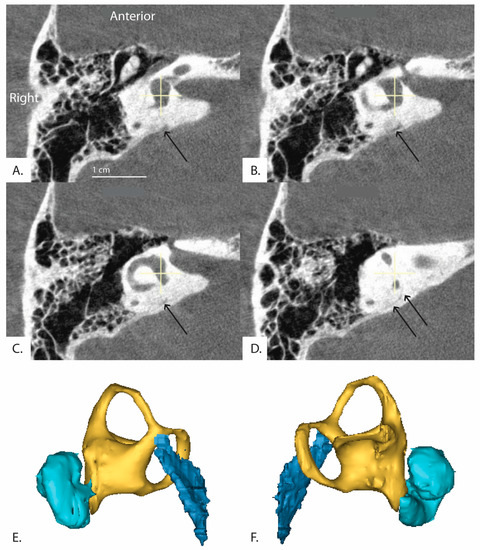

Additionally, in 30 patients, the distal vestibular aqueduct in the region of the operculum of one ear was determined too difficult to clearly visualize and measure when reformatted in the plane of the horizontal semicircular canal, even in these high resolution CT images. Figure 5 shows a patient whose distal vestibular aqueduct was unidentifiable in the image stack. Figure 6A–D demonstrates how although the image was captured in the plane of the horizontal semicircular canal, the distal portion of the vestibular aqueduct is not visible and takes a complicated trajectory through the bone. In addition, often the vestibular aqueduct is visualized as a small wedge-shaped figure (Figure 6A–D) that may be a representation of the vestibular aqueduct directly parallel to its entering the temporal bone rather than a visualization of the vestibular aqueduct perpendicular to its travel through the bone. This is partially accounted for by the software as there is an option to use both an image at the level of the vestibule and if the distal aqueduct is not visible in that image, another image at the level of the distal VA to measure .

Figure 6.

(Patient 16R) A series of sequential CT images of the inner ear reformatted in the plane of the horizontal semicircular canal are shown. The series runs clockwise from top left (A–D) and progresses inferior to superior. The distal vestibular aqueduct is unable to be visualized at the level of the vestibule but is shown in the image stack. Black arrows indicate the path of the vestibular aqueduct. (E,F) demonstrate 3D reconstruction of the vestibular aqueduct. (E) is a right view of the 3D model and (F) is a left view. Cyan colored shape is the cochlea, yellow is the vestibule and semicircular canals, and dark blue is the vestibular aqueduct.